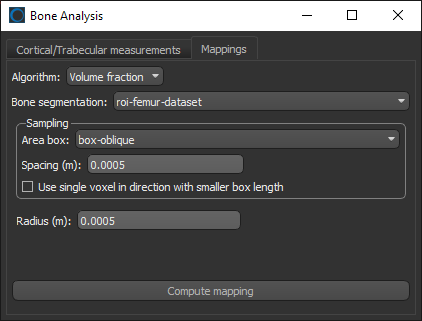

- Choose the settings for the volume fraction map on the Mappings tab, as shown below.

- Click the Compute mapping button.

When processing is complete, the volume fraction dataset appears on the Data Properties and Settings panel.